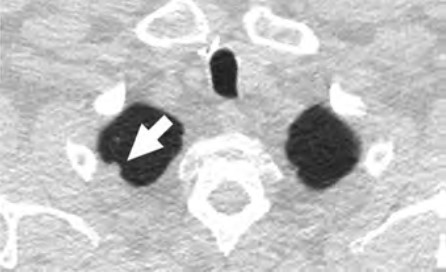

At the individual level, some of the barriers include decreased opportunities to provide accurate smoking history in the EMR, cost concerns related to insurance coverage of LCS and subsequent followups (Fig. 3), challenges to understanding LCS results when examinations show abnormal findings, fragmentation of care for management of abnormal LCS results and incidental findings, and difficulties navigating the complexities of health care systems [4, 8, 10]. Cost transparency and cost concerns are areas of active research, because cost influences how patients access and use health services [2]. For example, a recently published study evaluated the out-of-pocket cost of invasive procedures after LCS and showed that the rates of invasive procedures in commercially insured populations exceed those of invasive procedures in clinical trial participants [2].